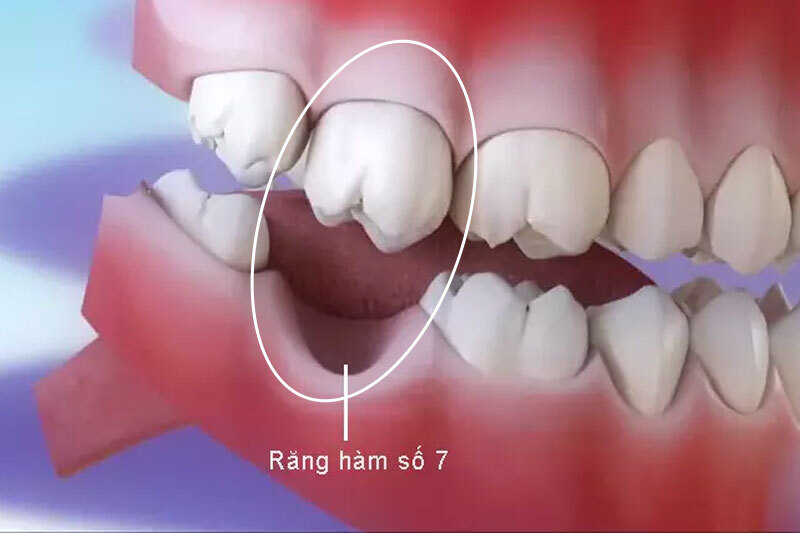

2.5 Mất răng số 7 có niềng răng được không?

Răng số 7 là răng hàm trong cùng. Khi mất răng này, ảnh hưởng đến khớp cắn thường không quá nghiêm trọng nếu răng số 6 còn khỏe. Nhiều trường hợp vẫn có thể niềng bình thường mà không cần trồng lại răng số 7, trừ khi mất răng hai bên gây lệch khớp cắn.

Răng số 6 là răng chịu lực chính của cung hàm. Khi mất răng này lâu ngày, dễ xảy ra:

- Tiêu xương ổ răng

- Răng số 7 nghiêng đổ

- Răng đối diện trồi xuống